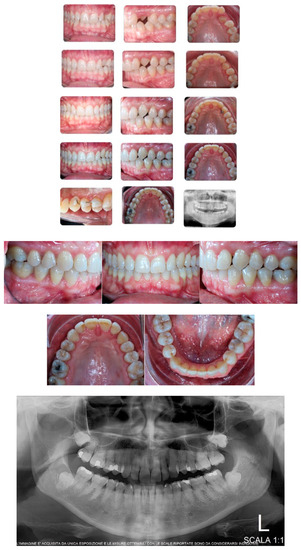

A 16-year-old male patient presented with a Class I occlusion, mild crowding, deep bite, and missing upper left cuspid with the absence of the respective deciduous. Light crowding can be detected in the maxillary arch, whereas no crowding was detected in the mandibular arch. The maxillary midline was coincident with the face and the mandibular midline. The radiographic analysis revealed a moderate impaction with a supernumerary tooth in the lower jaw between 3.5 and 3.4 ligually positioned and a skeletal Class I malocclusion with deep bite due to negative upper and lower incisors inclination.

Figure 1 shows an initial stage of treatment—the upper arch with the absence deciduous canine no. 63. The malposition of the teeth, such as distorotation of the incisors, vestibuloposition of the right canine, as well as an irregular and incorrect shape of the upper arch, are noticeable.

Pre-treatment records of the first patient.

Figure 2 panoramic and CBCT showing the moderate palatal 2.3 impaction. Lateral X-rays confirming a Class I skeletal and dental malocclusion with deep bite.

Cephalometric analysis, panoramic and CBCT of the first patient. Lateral X-rays confirming a Class I skeletal and dental malocclusion with deep bite.